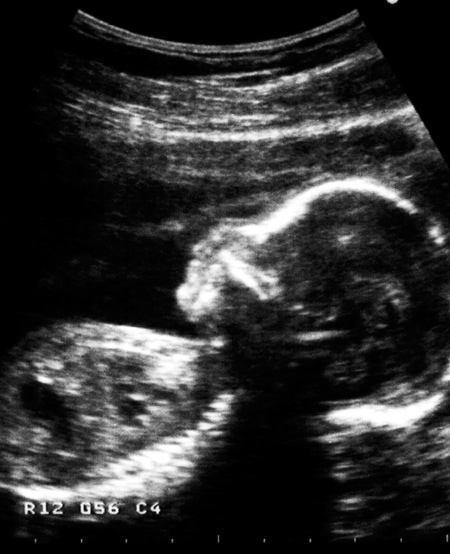

Redusert fostervekst i første trimester er forbundet med ugunstig kardiovaskulær risikoprofil i skolealder.

Illustrasjonsfoto: Elisabeth Edén/Bildhuset/TT